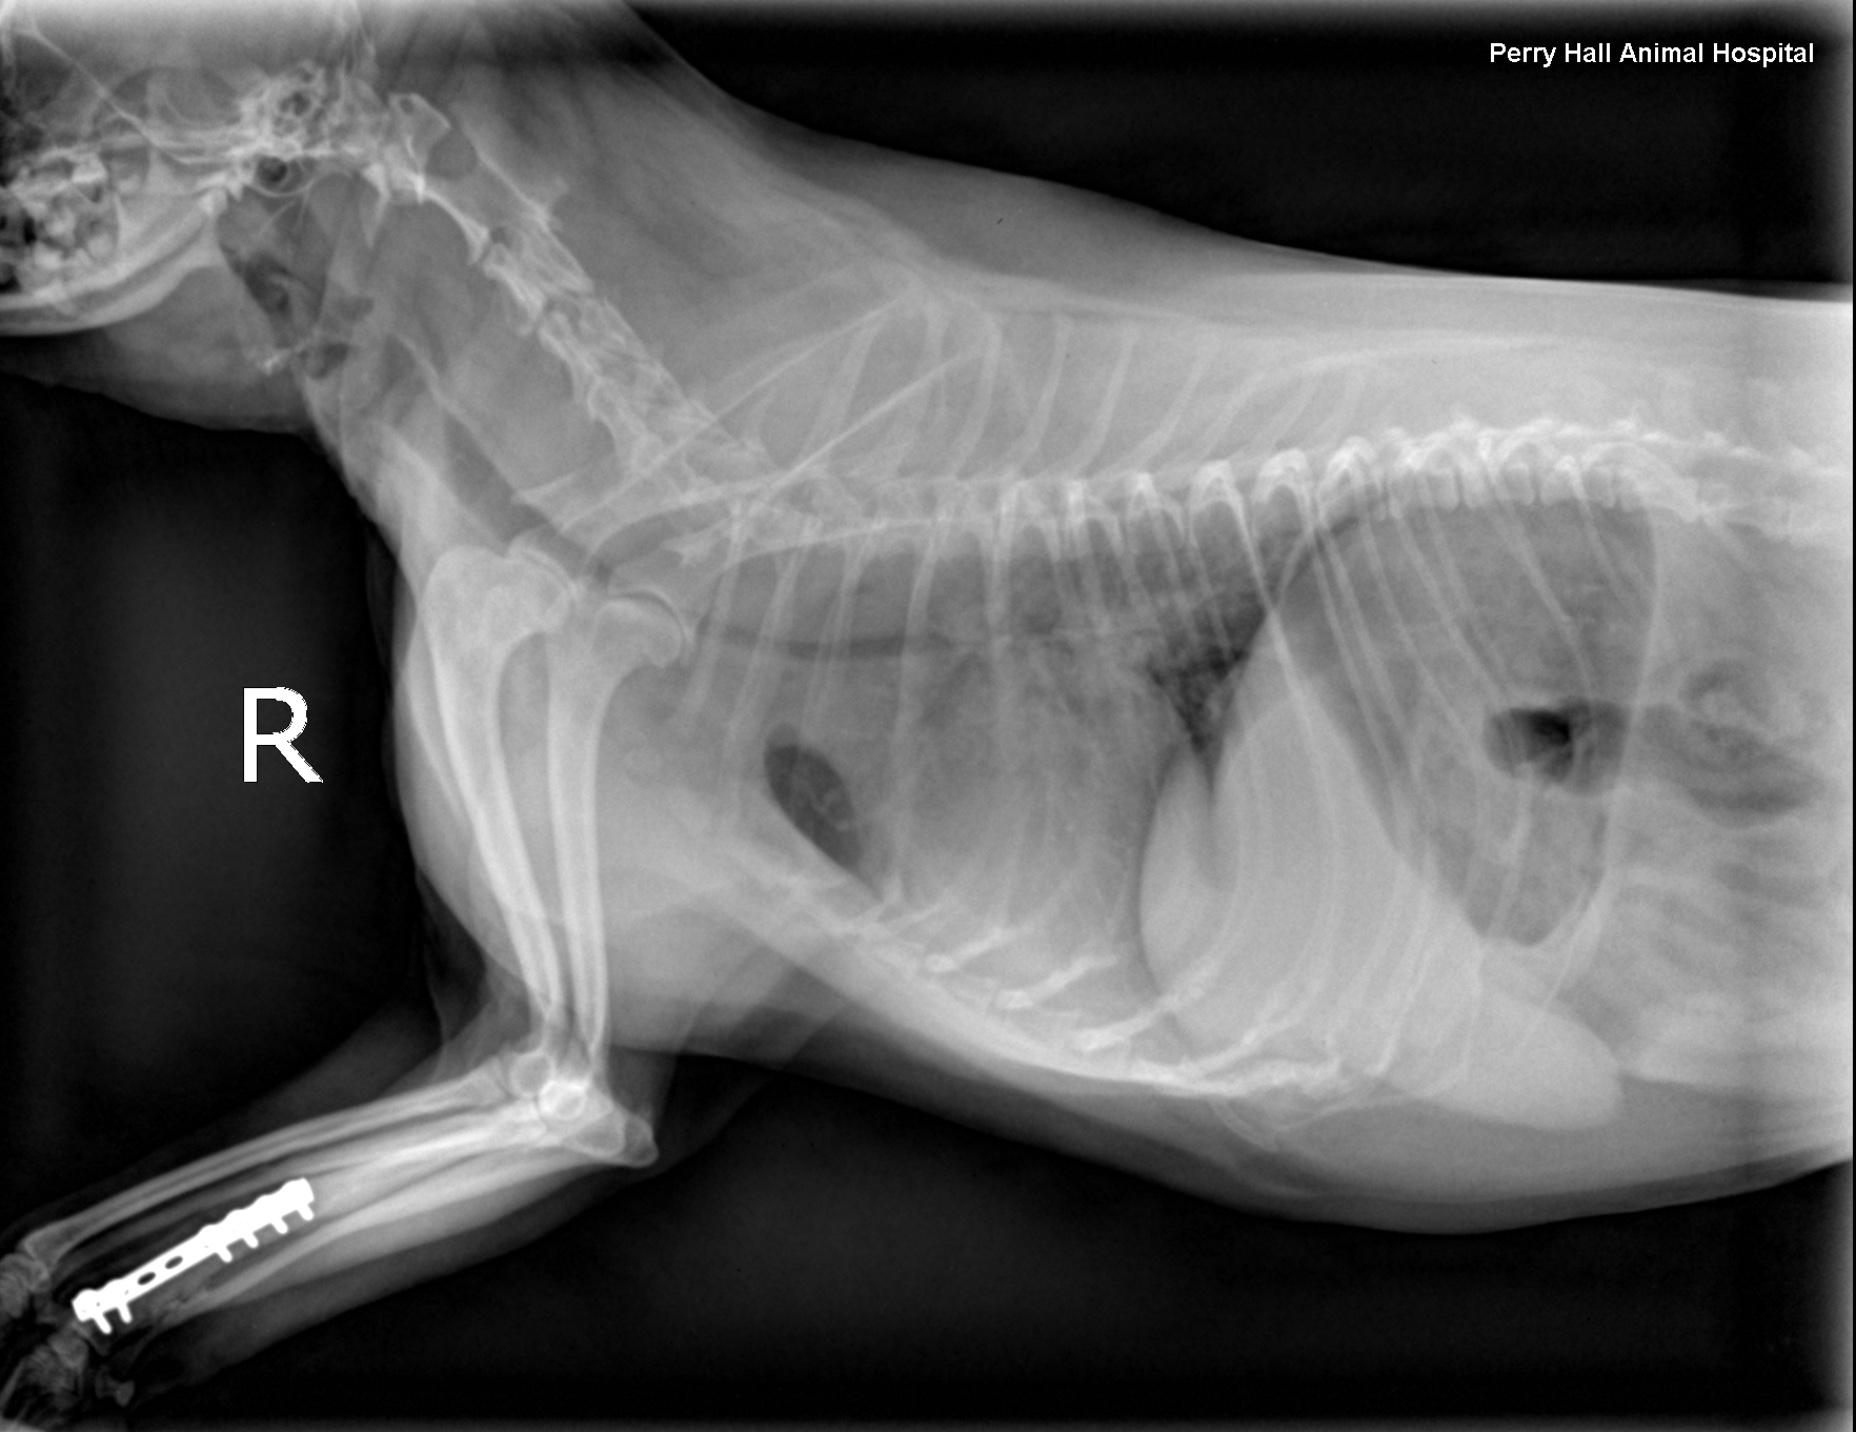

Rads- Left lateral, right lateral and VD views of the thorax and neck. One of the lateral views was obtained in fair inspiration (degree of inspiration reduced as a function of the disease), one was an expiratory view. There was mild to moderate rotation of the trunk in the lateral views. There was superimposition of the front limbs with the cranial thorax. The hands of the holding person were in the primary beam during exposure which is strictly prohibited.

Intrathoracic structures: The chest volume was small. There was an intrathoracic tracheal collapse and collapse of the main stem bronchi on the expiratory view. The height of the trachea was reduced by more than 50 % as compared with the inspiratory view. The tracheal lumen was reduced to a height of 2mm level with the thoracic inlet when collapsed. The cardiac silhouette was normal for size and shape. The major vessels were within normal limits. The pulmonary vessels and caudal vena cava were within normal limits. No mediastinal widening was noted.

The lungs showed diffuse increase in opacity caudodorsally on the expiratory view

The radiographic findings are compatible with dynamic tracheal and bronchial collapse likely due to bronchomalacia.